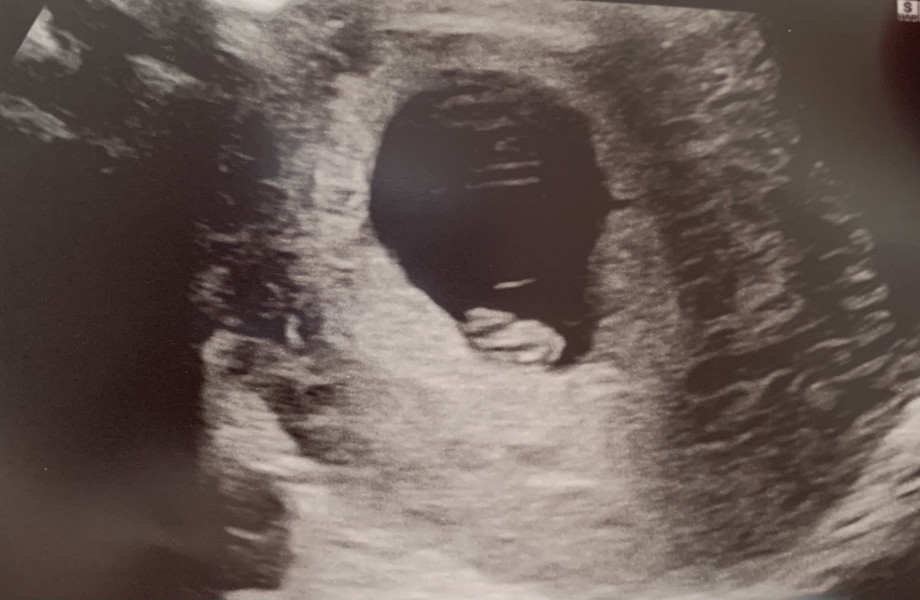

Scan went well this morning. Saw the heartbeat and the picture was much clearer on screen. Glad everything is currently healthy ❤️ based on LMP I should be 8+2 but from ovulation I should be 7+3 which is exactly where the scan measured so I'm happy it's not behind that

Congrats @RSmamaa what a lovely clear scan!

Lovely to see such a clear scan photo @RSmamaa. A good start to your weekend!